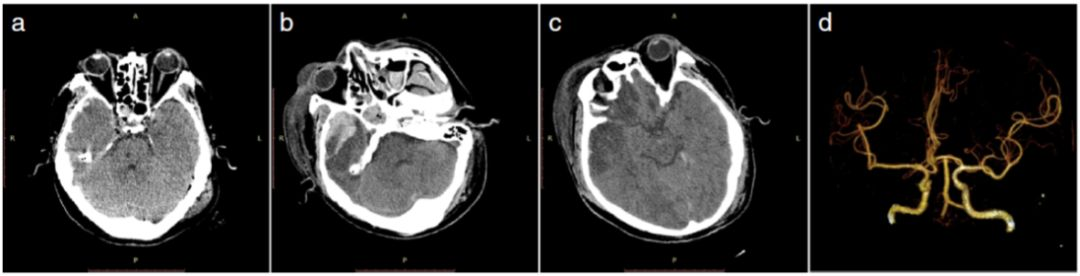

45岁男性患者,因车祸头部受伤。入院后GCS评分8分;头颅CT检查示,右侧额颞部硬膜下血肿合并右侧额颞叶小血肿,占位效应不明显。入院第二天GCS评分12分,头颅CT复查可见右侧颞叶内血肿增大伴额颞叶脑梗死,头颅CTA未发现颅内主要动脉异常改变。入院第三、四天头颅CT扫描发现脑梗死范围扩大,有明显占位效应,GCS评分下降至9分,遂行右侧额颞去骨瓣减压术(图1)。

图1. 创伤后第一、第二天头部CT表现:a.入院时头部CT:右侧额颞部硬膜下血肿合并右侧额颞叶血肿;b.入院第二天脑内血肿增大;c.出现创伤性脑梗死;d.头部CTA。